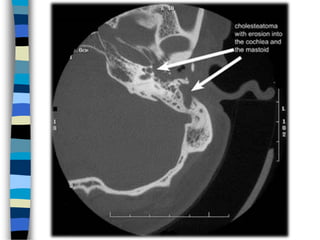

Холестеотом НянЧихний хулхи Идээ

Холестеотом

Оношлогоо Чихний тольдолт

Сонсголын шинжилгээ Нянгийн шинжилгээ Рентген КТГ СРТГ